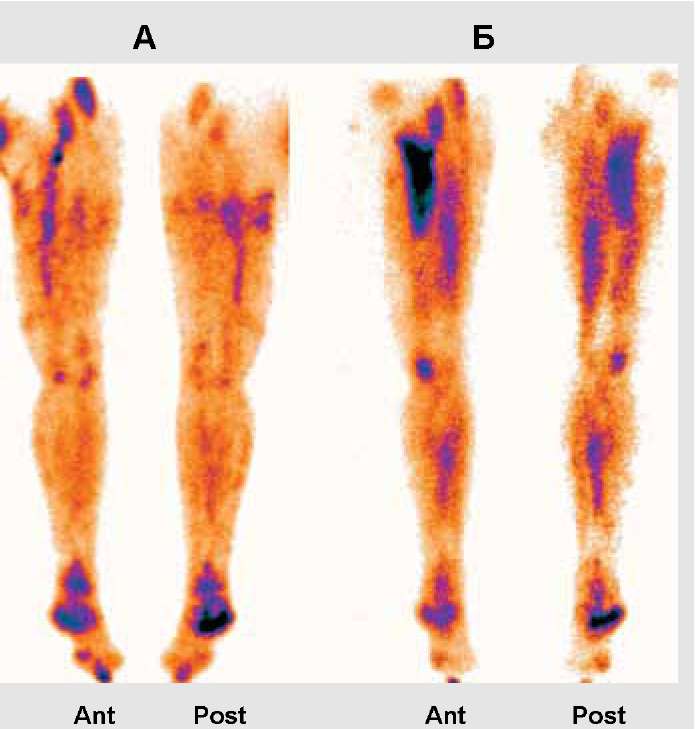

Изображения, связанные с атеросклерозом нижних конечностей и его лечением